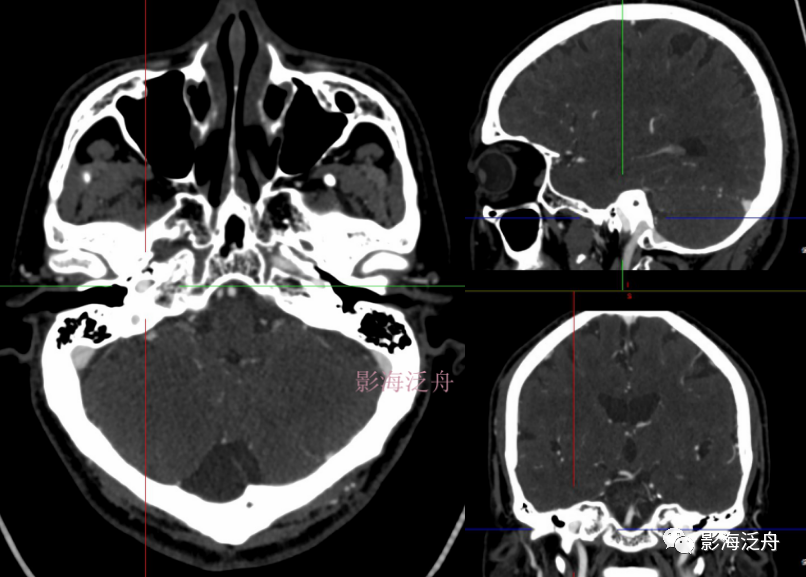

f9bc0946cb9a65ef5d20bd9f751f9506.png

342e36df4f41edc985dee562e77a68de.png

C3段(破裂孔段),是一段没有分支的短段。该段的识别需要在轴位CT中准确找到破裂孔的位置(红虚线处)。

0ebb11bf62cfc06fc505b68fe2d76352.png

通过这幅图,再强化一下对破裂孔的认识。

07c151aa1927eaa978659a26e5fbbcd3.png

破裂孔靠上一个层面,属于C3段。

C3段识别特征:在轴位CT上,破裂孔层面+靠上的一个或者两个(具体看扫描层厚)层面共同构成C3段。